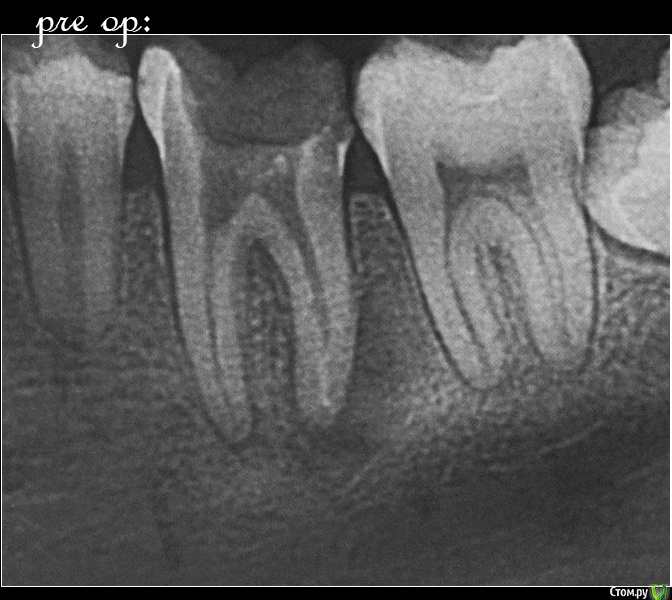

M@estro Опубликовано 9 июля, 2015 Автор Поделиться Опубликовано 9 июля, 2015 Тоже подниму тему. Травму отрицает, жалобы на потемнение. Витальность "-", перкуссия "-" , на рентгене подсказка - есть латераль. Вперёд, мыть ! 60 апекс, гибрид паковка. 1 час с пломбой 7 Ссылка на комментарий

M@estro Опубликовано 23 июля, 2015 Автор Поделиться Опубликовано 23 июля, 2015 И сюда закину Жалобы на боли, КЕСТУ и желание " удалить " . Зуб 3.6 . Пациент - парнишка 16 лет. Зуб ранее пытались лечить,парень признался, что было больно, и больше он туда не вернулся, а в другой клинике предложили удалить зуб , ибо "кЕста". Перкуссия - резко-болезненна , в полости зуба - остатки ватки. В первое посещение - билд, обработка каналов ( дистальный 70/02 , медиальные 50 / 02) , антисептика, кальций на 2 недели . Второе посещение - обтурация , в дистальном -" неаккуратненько", плюнул силер. Следом бюджетная мк коронка. Контрольный через 4 месяца. 9 Ссылка на комментарий